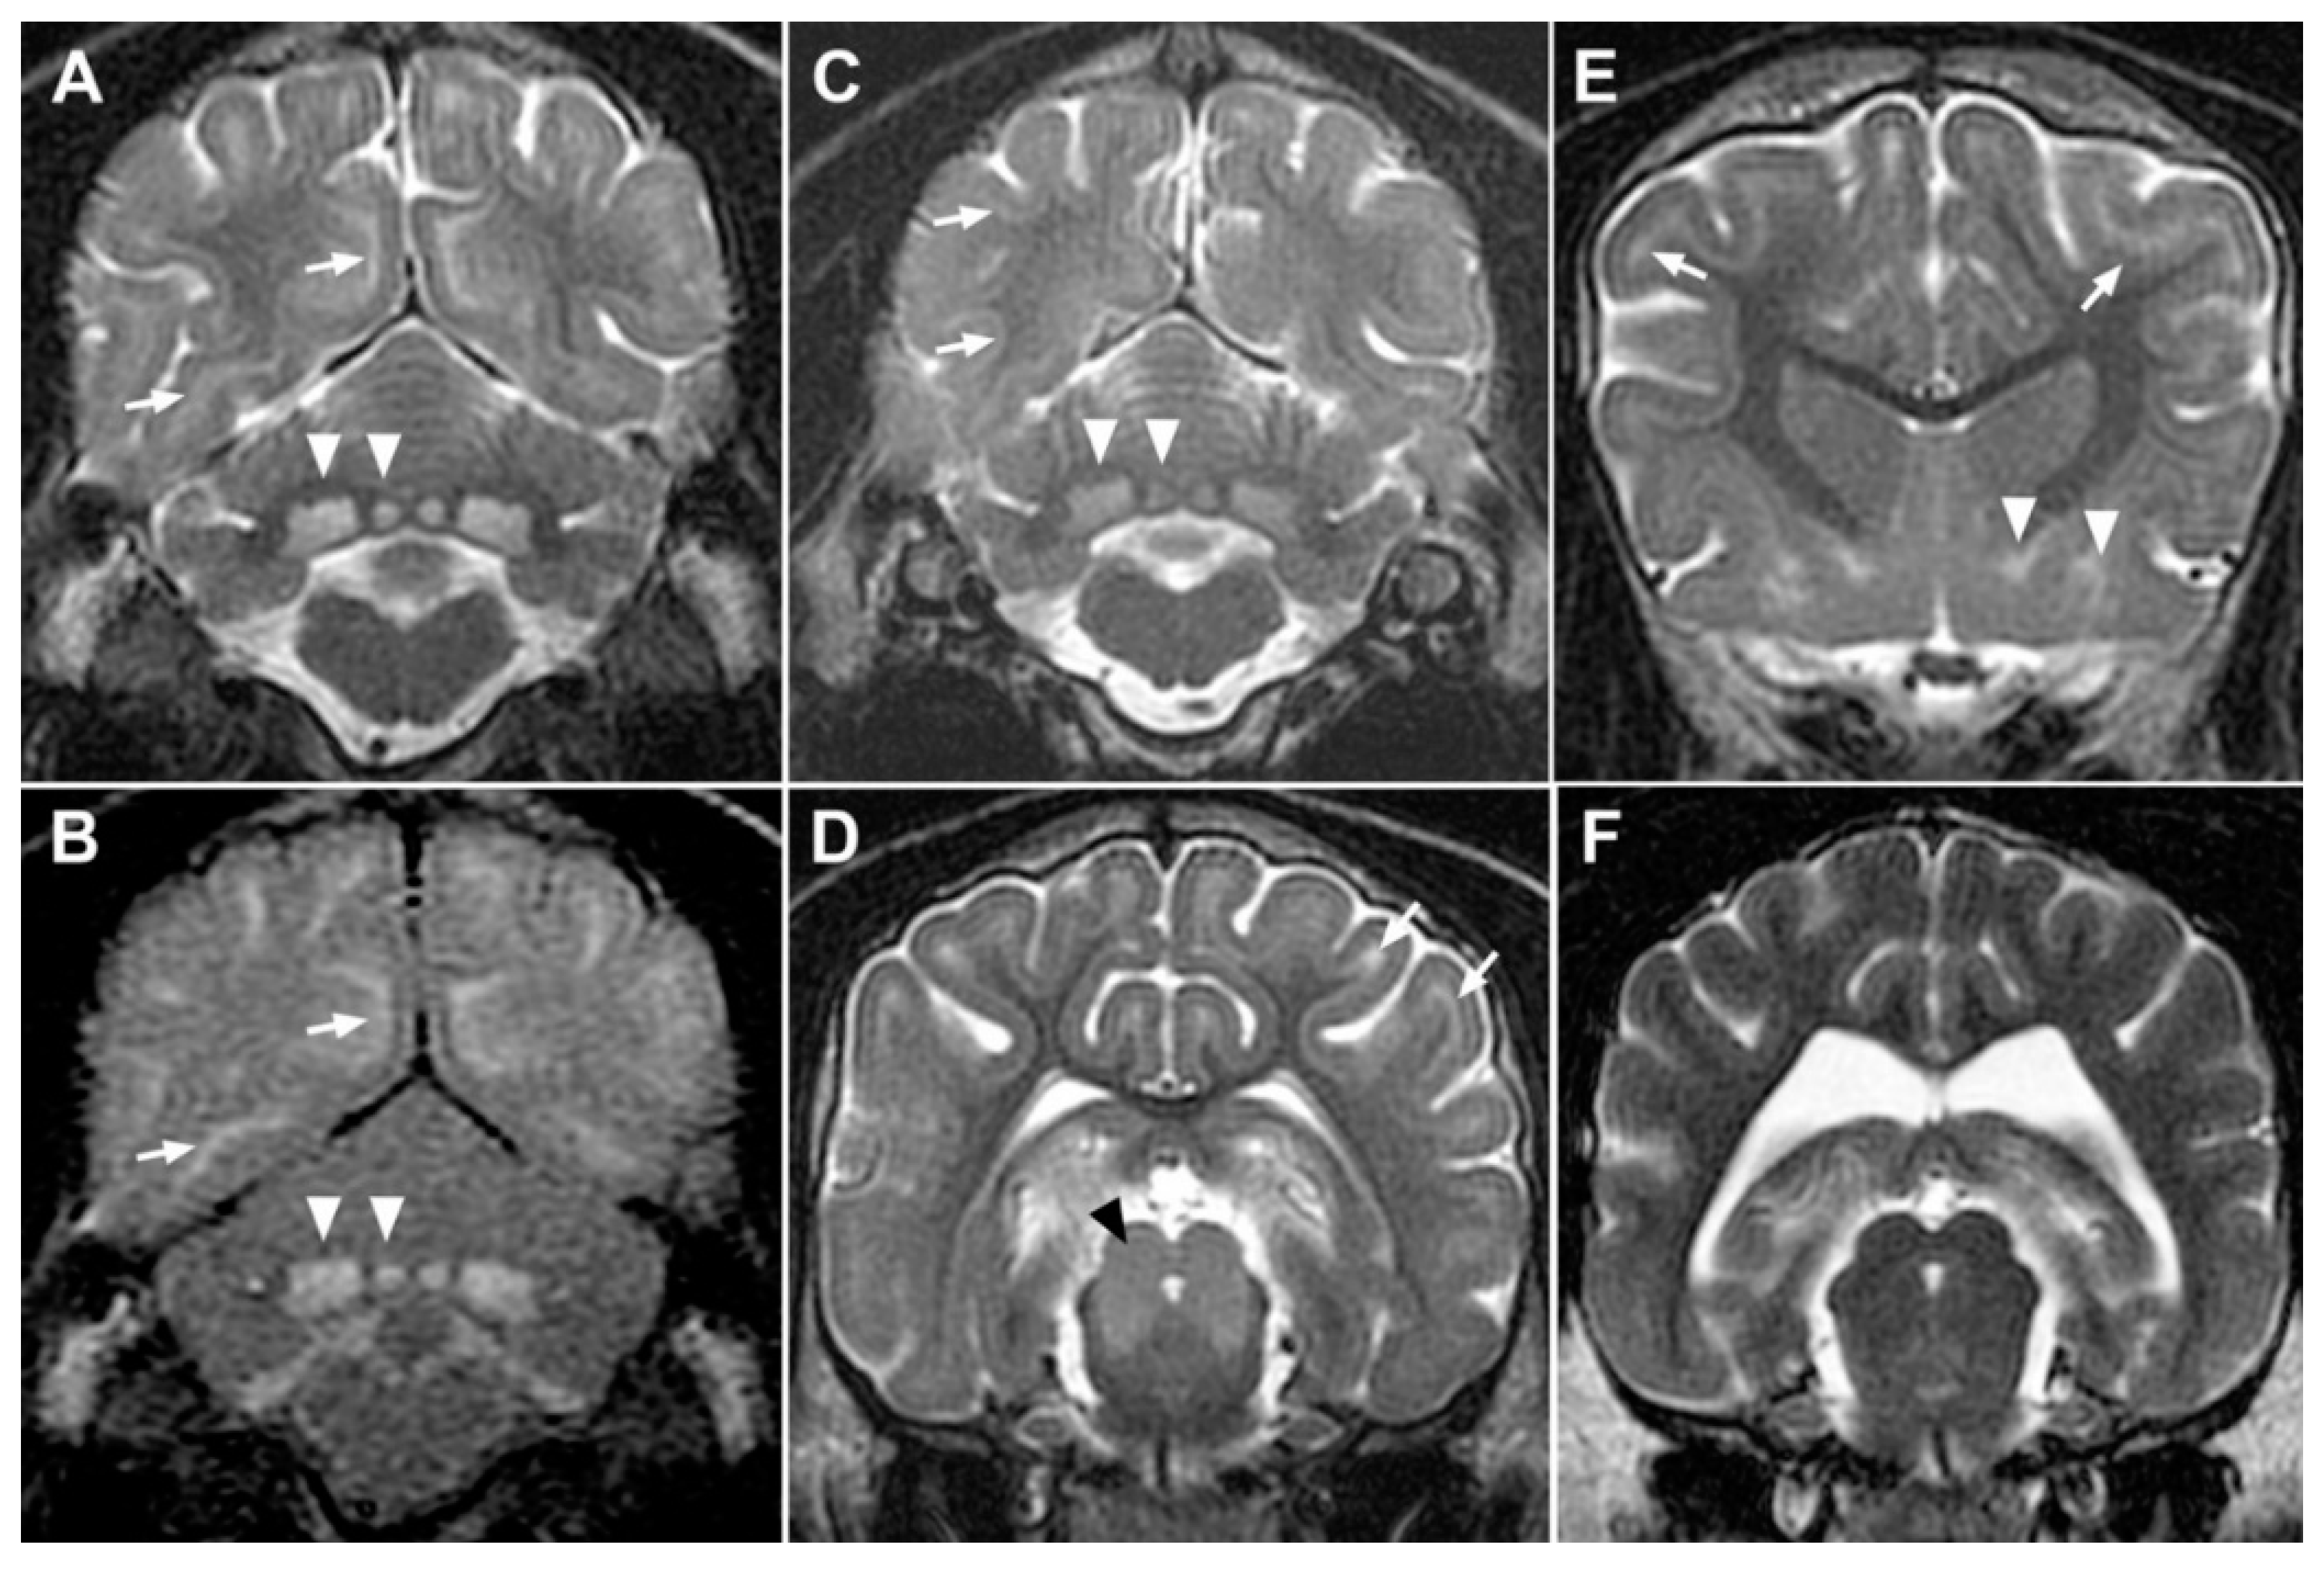

3.3. MRI and Histopathology